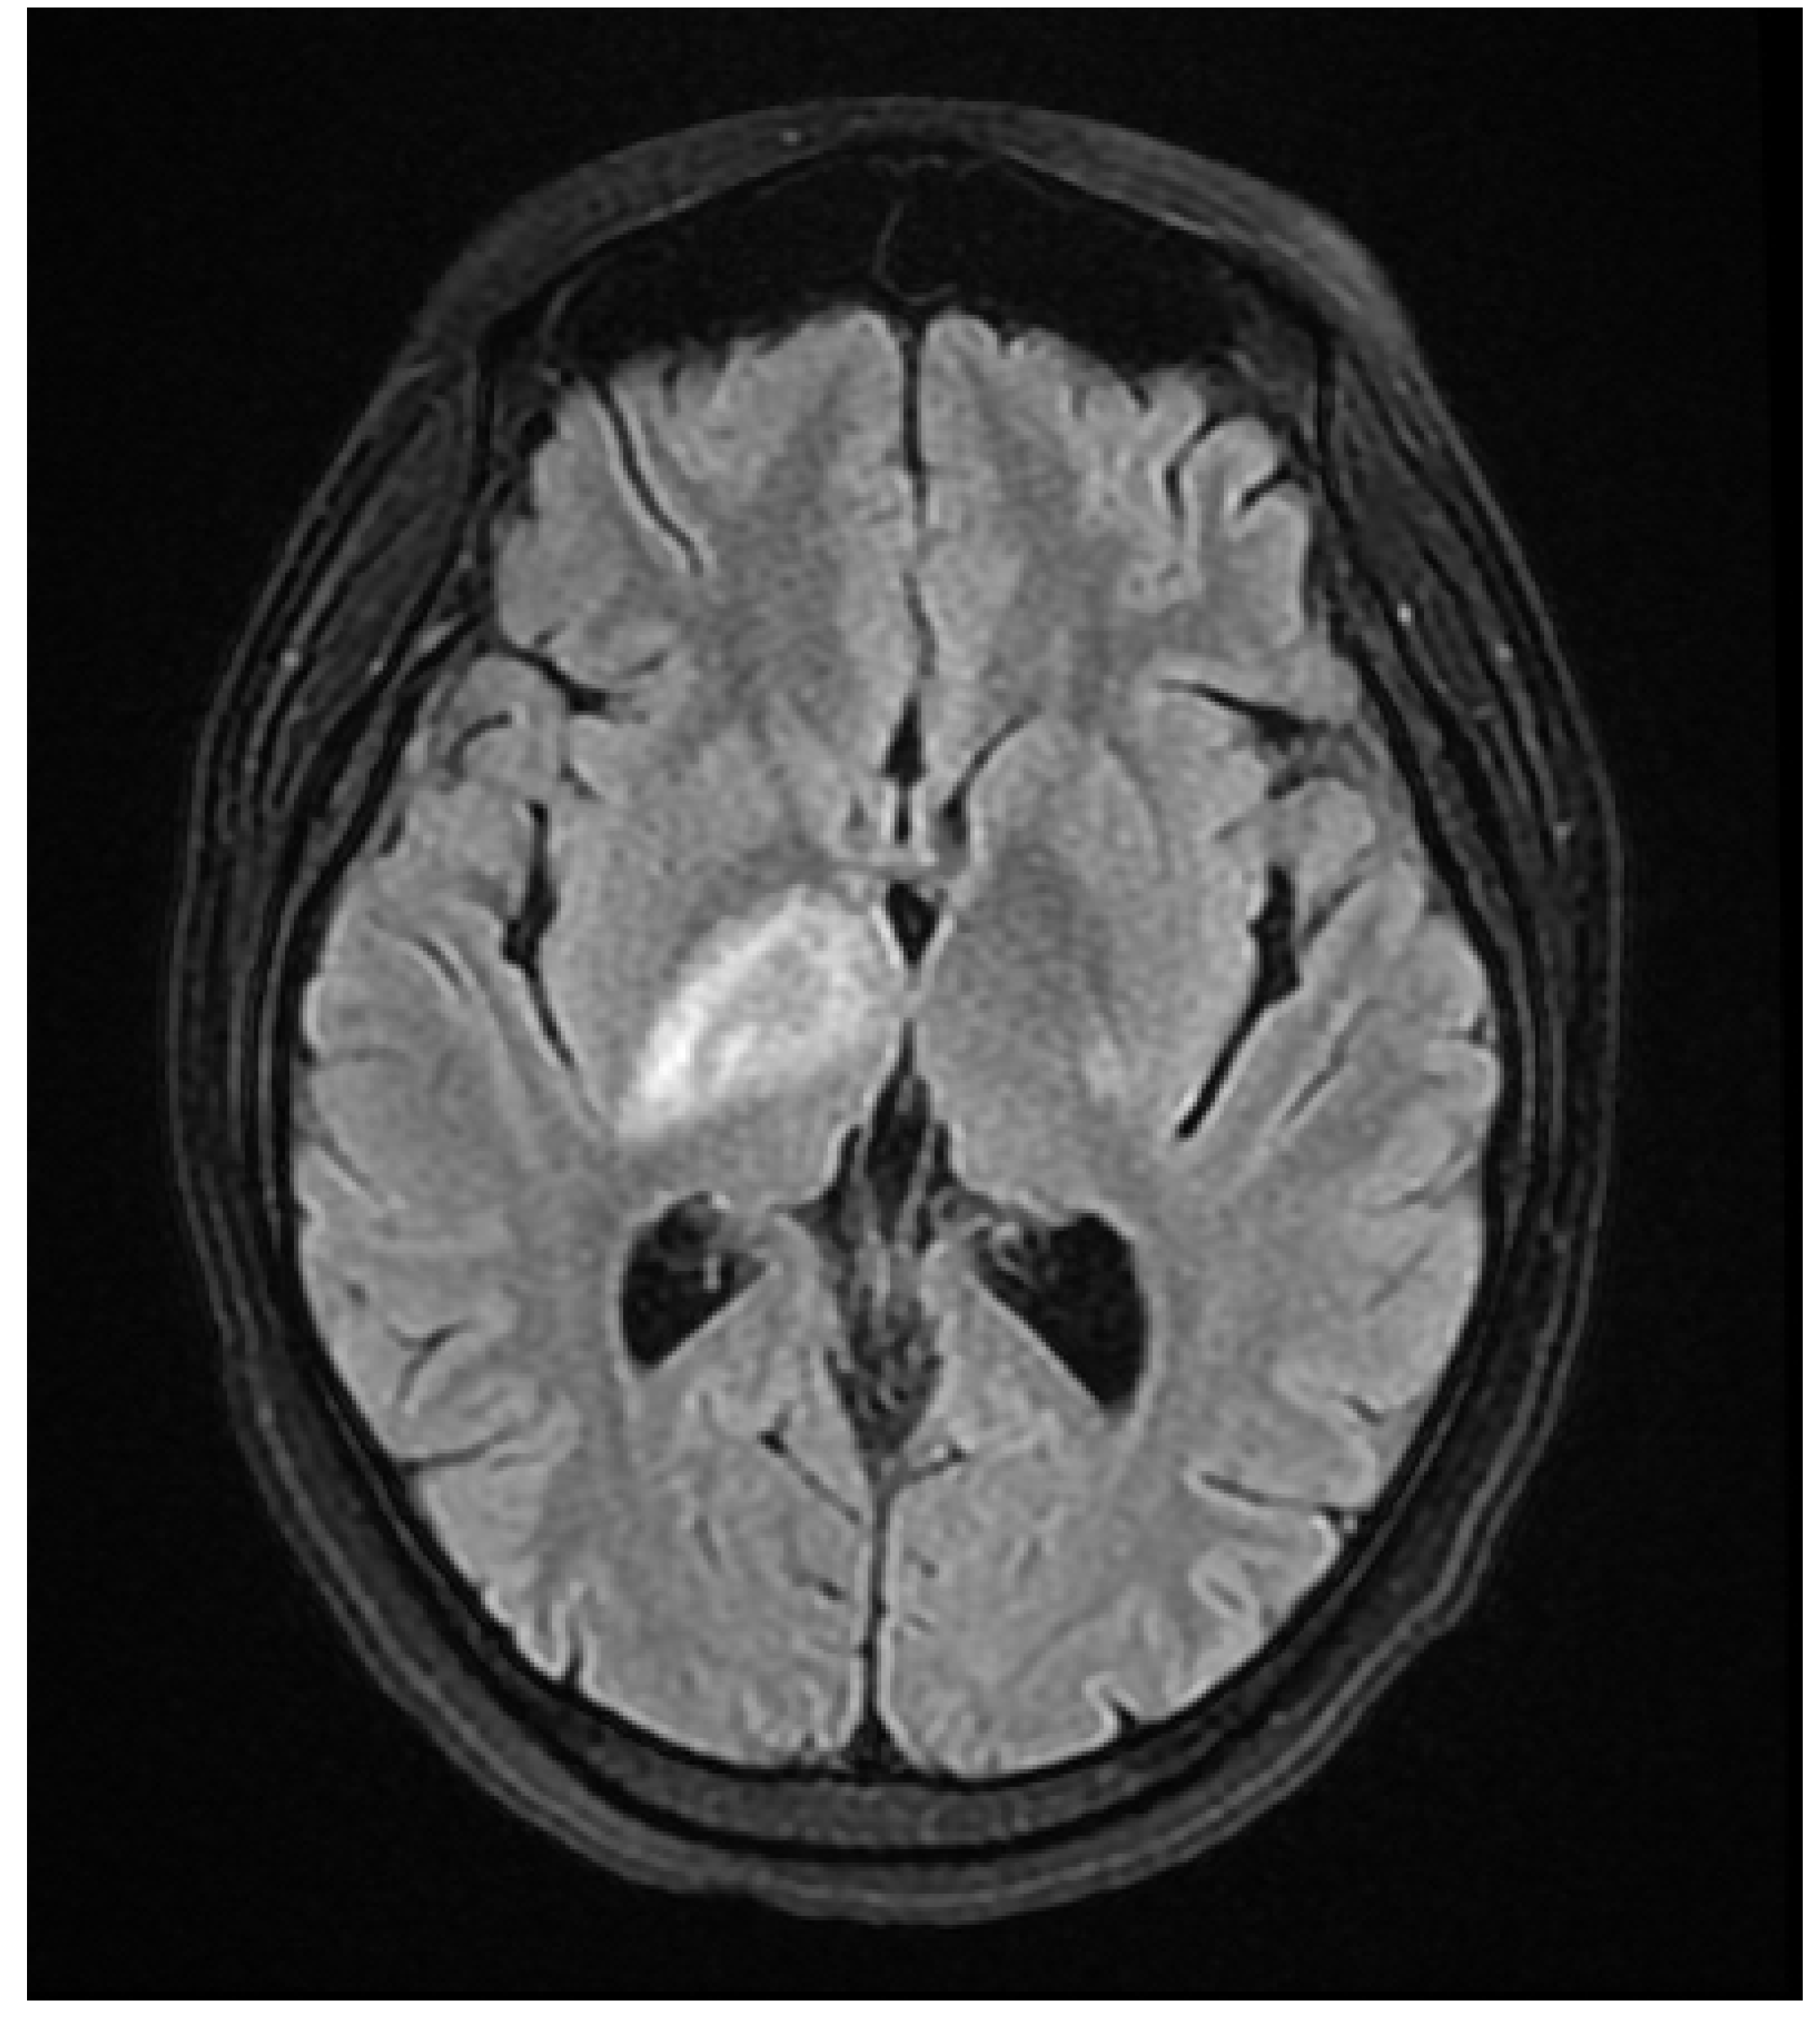

A 37 year old female presented to our hospital due to new onset severe headaches and right sided weakness with facial droop. The patient did not have any significant past medical history before this point. Patient was unable to speak properly and was found to have decreased responsiveness at bedside. Initial CT scan of the head without contrast revealed ill-defined edema involving the left periatrial white matter, involving the central gray matter and external limited internal capsule. MRI head with T2 Flair revealed diffuse edema and inflammation throughout the brainstem, pons, midbrain, and basal ganglia (Figure 1, Figure 2, Figure 3 and Figure 4). EEG showed diffuse slowing suggestive of moderate diffuse cerebral dysfunction without evidence of seizures or epileptiform activity. Lumbar puncture demonstrated a normal opening pressure, with CSF containing 2 red blood cells, 9 white blood cells of which 94% were lymphocytes, glucose of 58, and protein of 42. CSF bacterial cultures were negative, along with no evidence of active HSV or EBV infection. RPR was also negative. Pulse dose steroids were initiated in the ICU. Patient was slow to improve and was transferred to the neurological intensive care unit for further management. After 17 days in the ICU patient was discharged to a rehabilitation facility. Patient slowly improved with physical therapy but did continue to have some refractory lower extremity weakness. At the time of discharge, our patient was discharged on 20mg prednisone daily. Outpatient brain biopsy of the right frontal cortex revealed moderate gliosis but no abnormal lymphocytic infiltration. After thorough review of imaging findings and clinical presentation a diagnosis of acute disseminated encephalomyelitis was made by Neurology.

Figure 3. Flair Axial MRI image reveals white matter lesions in the basal ganglia.